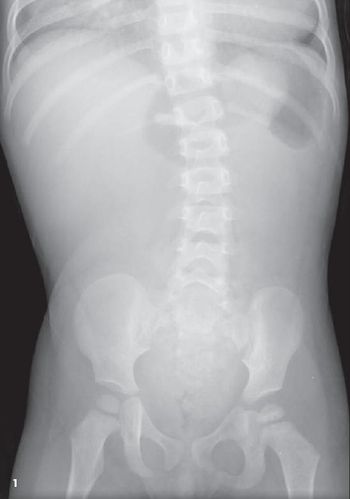

Twenty-two-month-old girl seen in the emergency department (ED) after several hours of abdominal pain associated with non-bloody, non-bilious emesis. Over past 2 months, has had 7 or 8 similar episodes of abdominal pain followed by emesis 1 to 2 hours later.